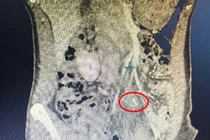

Qua khai thác bệnh sử, bệnh nhân cho biết trước đó có ăn cháo cá. Nhận thấy các dấu hiệu bất thường, các bác sĩ đã tiến hành thăm khám lâm sàng kết hợp thực hiện các xét nghiệm cần thiết. Kết quả chụp cắt lớp vi tính (MSCT) ổ bụng cho thấy một dị vật dạng xương cá xuyên qua thành ruột non, gây thủng ruột.

xuong-ca.jpg

Xương cá đâm thủng ruột bệnh nhân - Ảnh BVCC